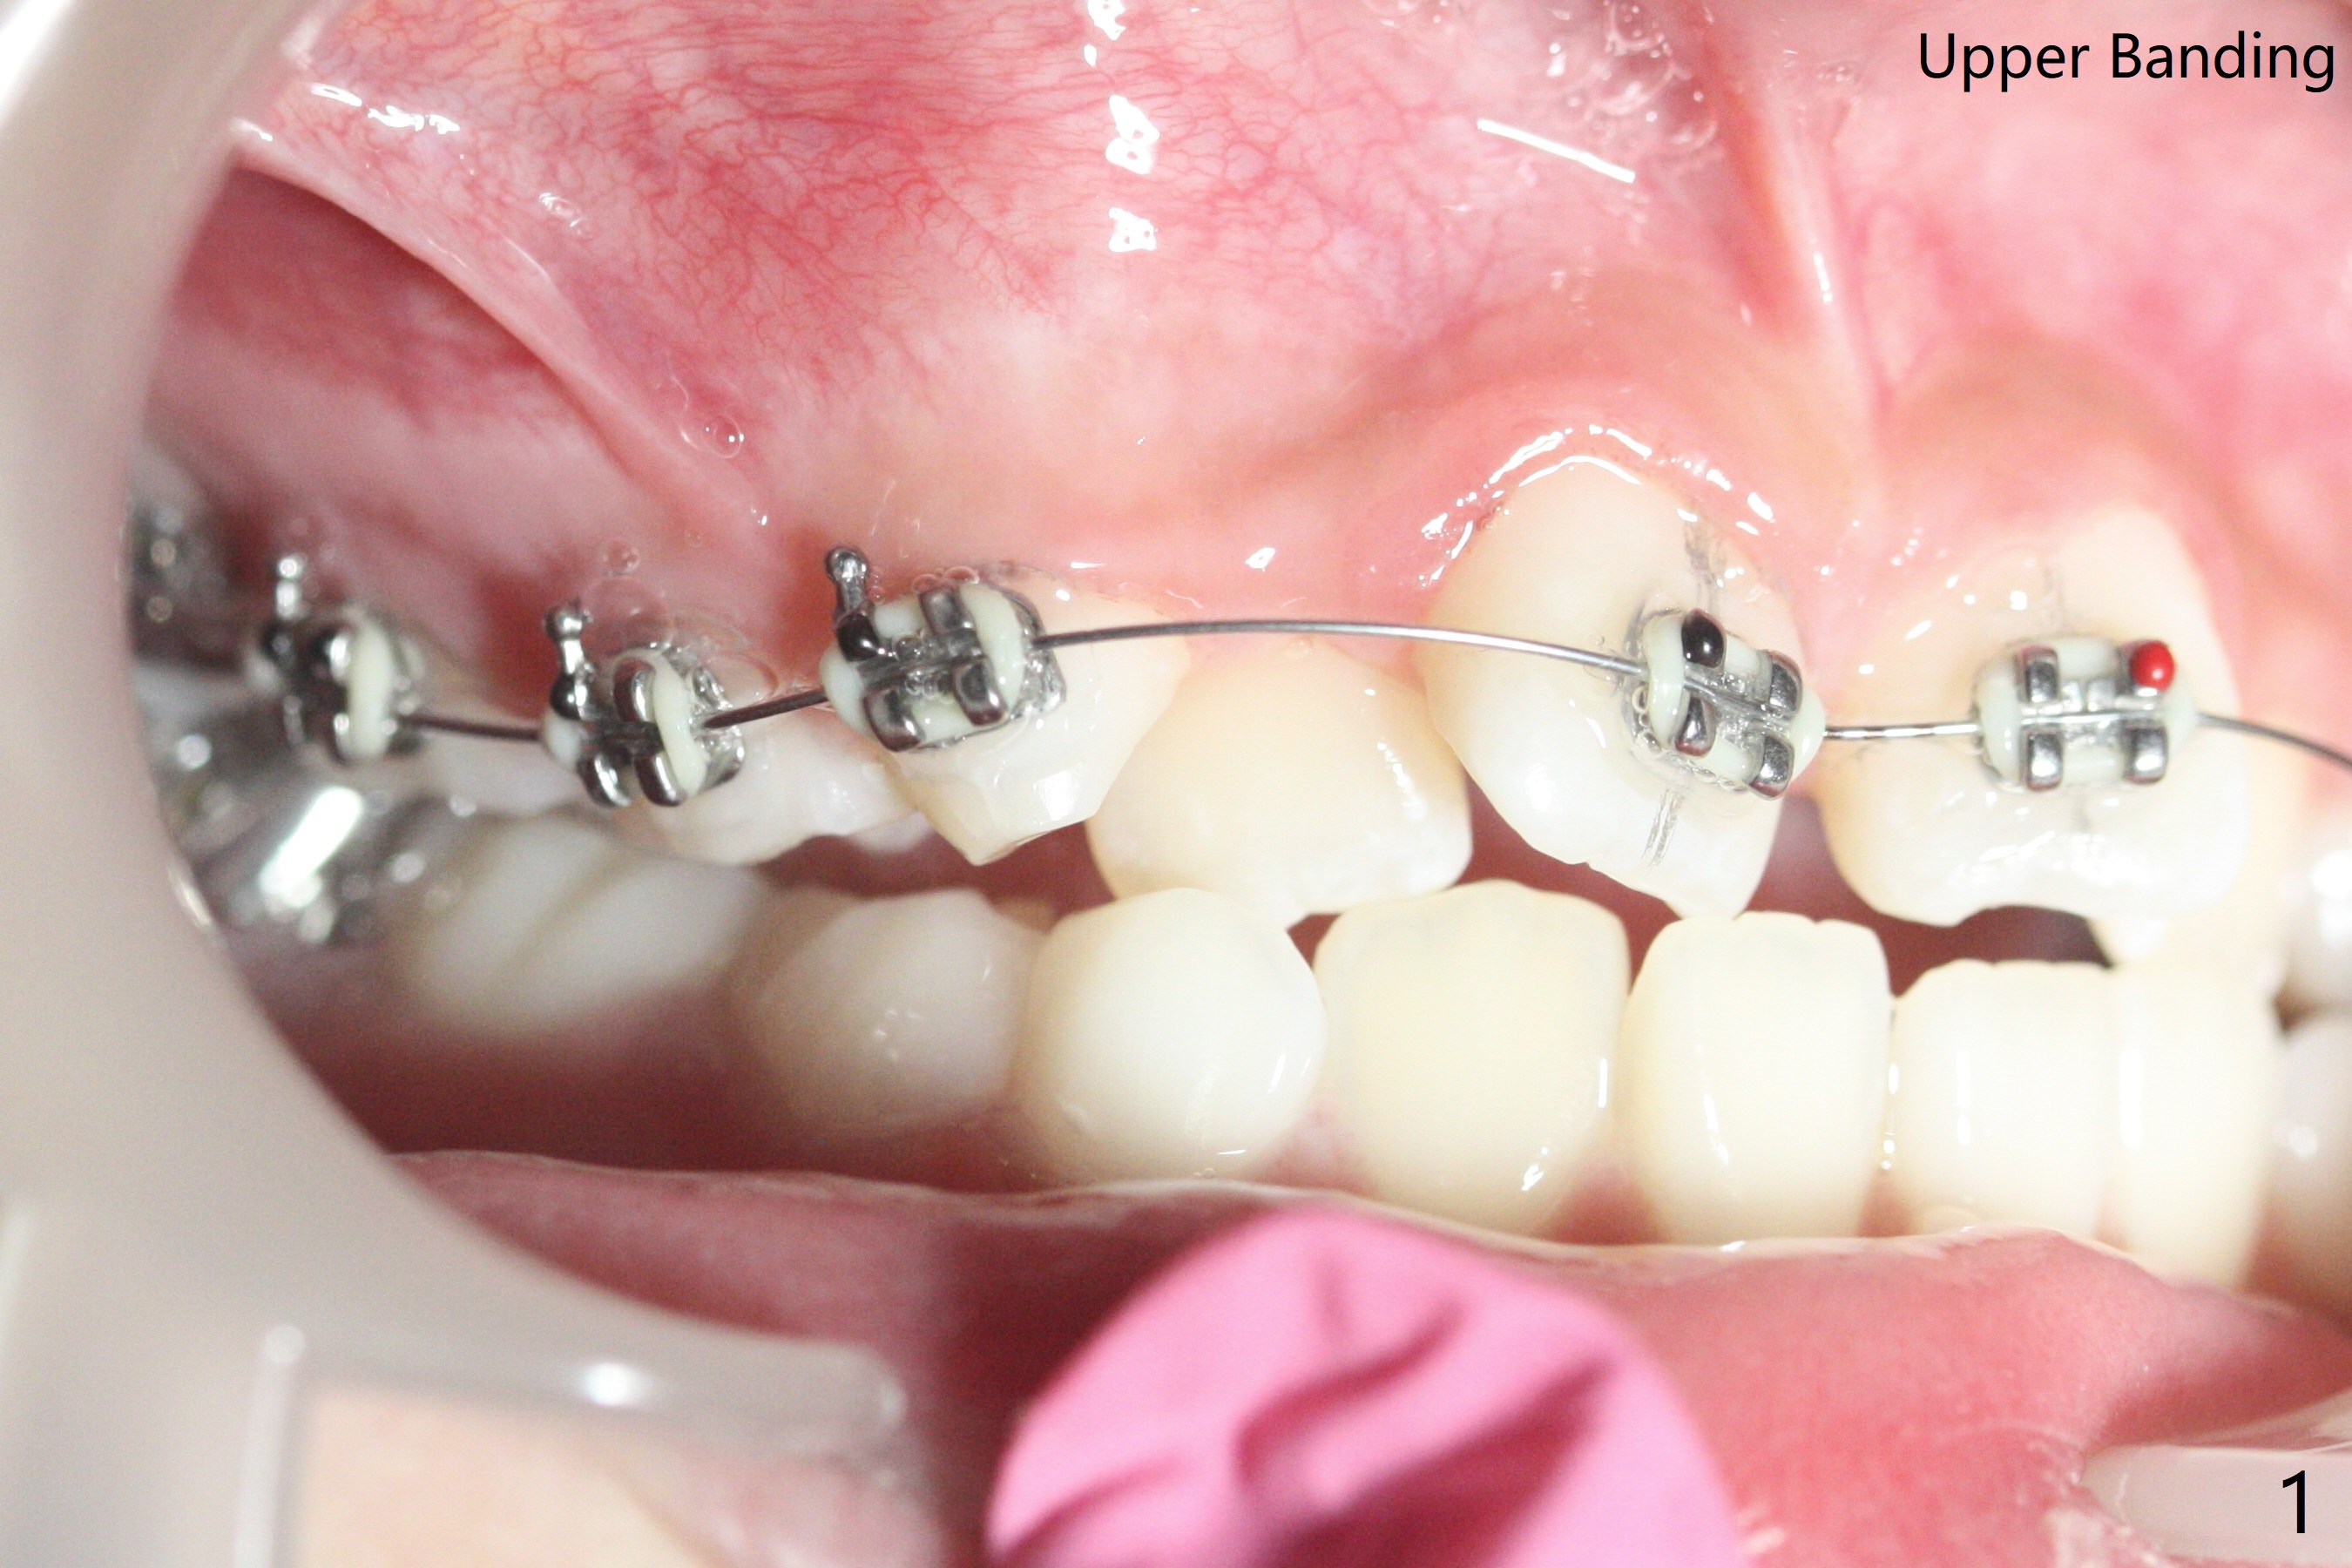

由于上颌拥挤严重,先放置矫正器(图一至三(.012));右上2空间小,可能需要从4近中片切获得,右边open coil spring应该比左边长。